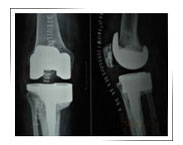

Non union fracture lateral tibial condyle in a 70yr old female :

Before Surgery

Implant with metal wedge